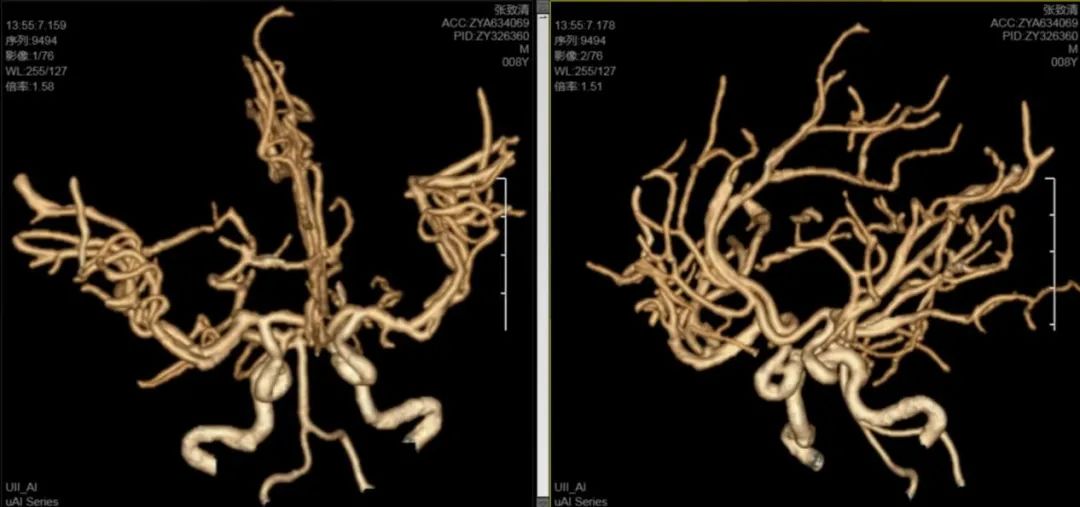

神经外科医疗中心吴鹏副院长解释道:小儿脑出血在临床上较为复杂,常见原因包括脑血管畸形、动脉瘤、血液系统疾病等,其中脑血管畸形最常见,处理较为复杂,手术风险极高。为进一步明确病因,排除脑血管畸形、动脉瘤等可能,立即为患儿进行了头颅CTA检查,结果未发现明显异常。